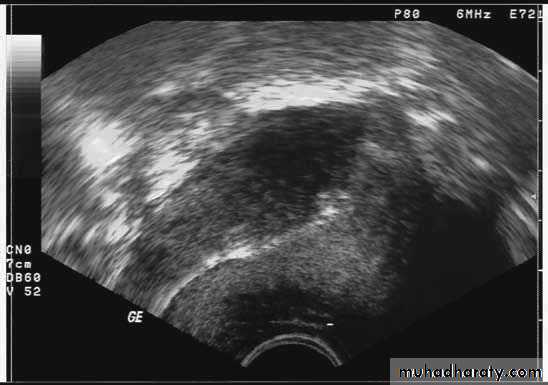

Ultrasound imaging

Copper IUDLNG IUD